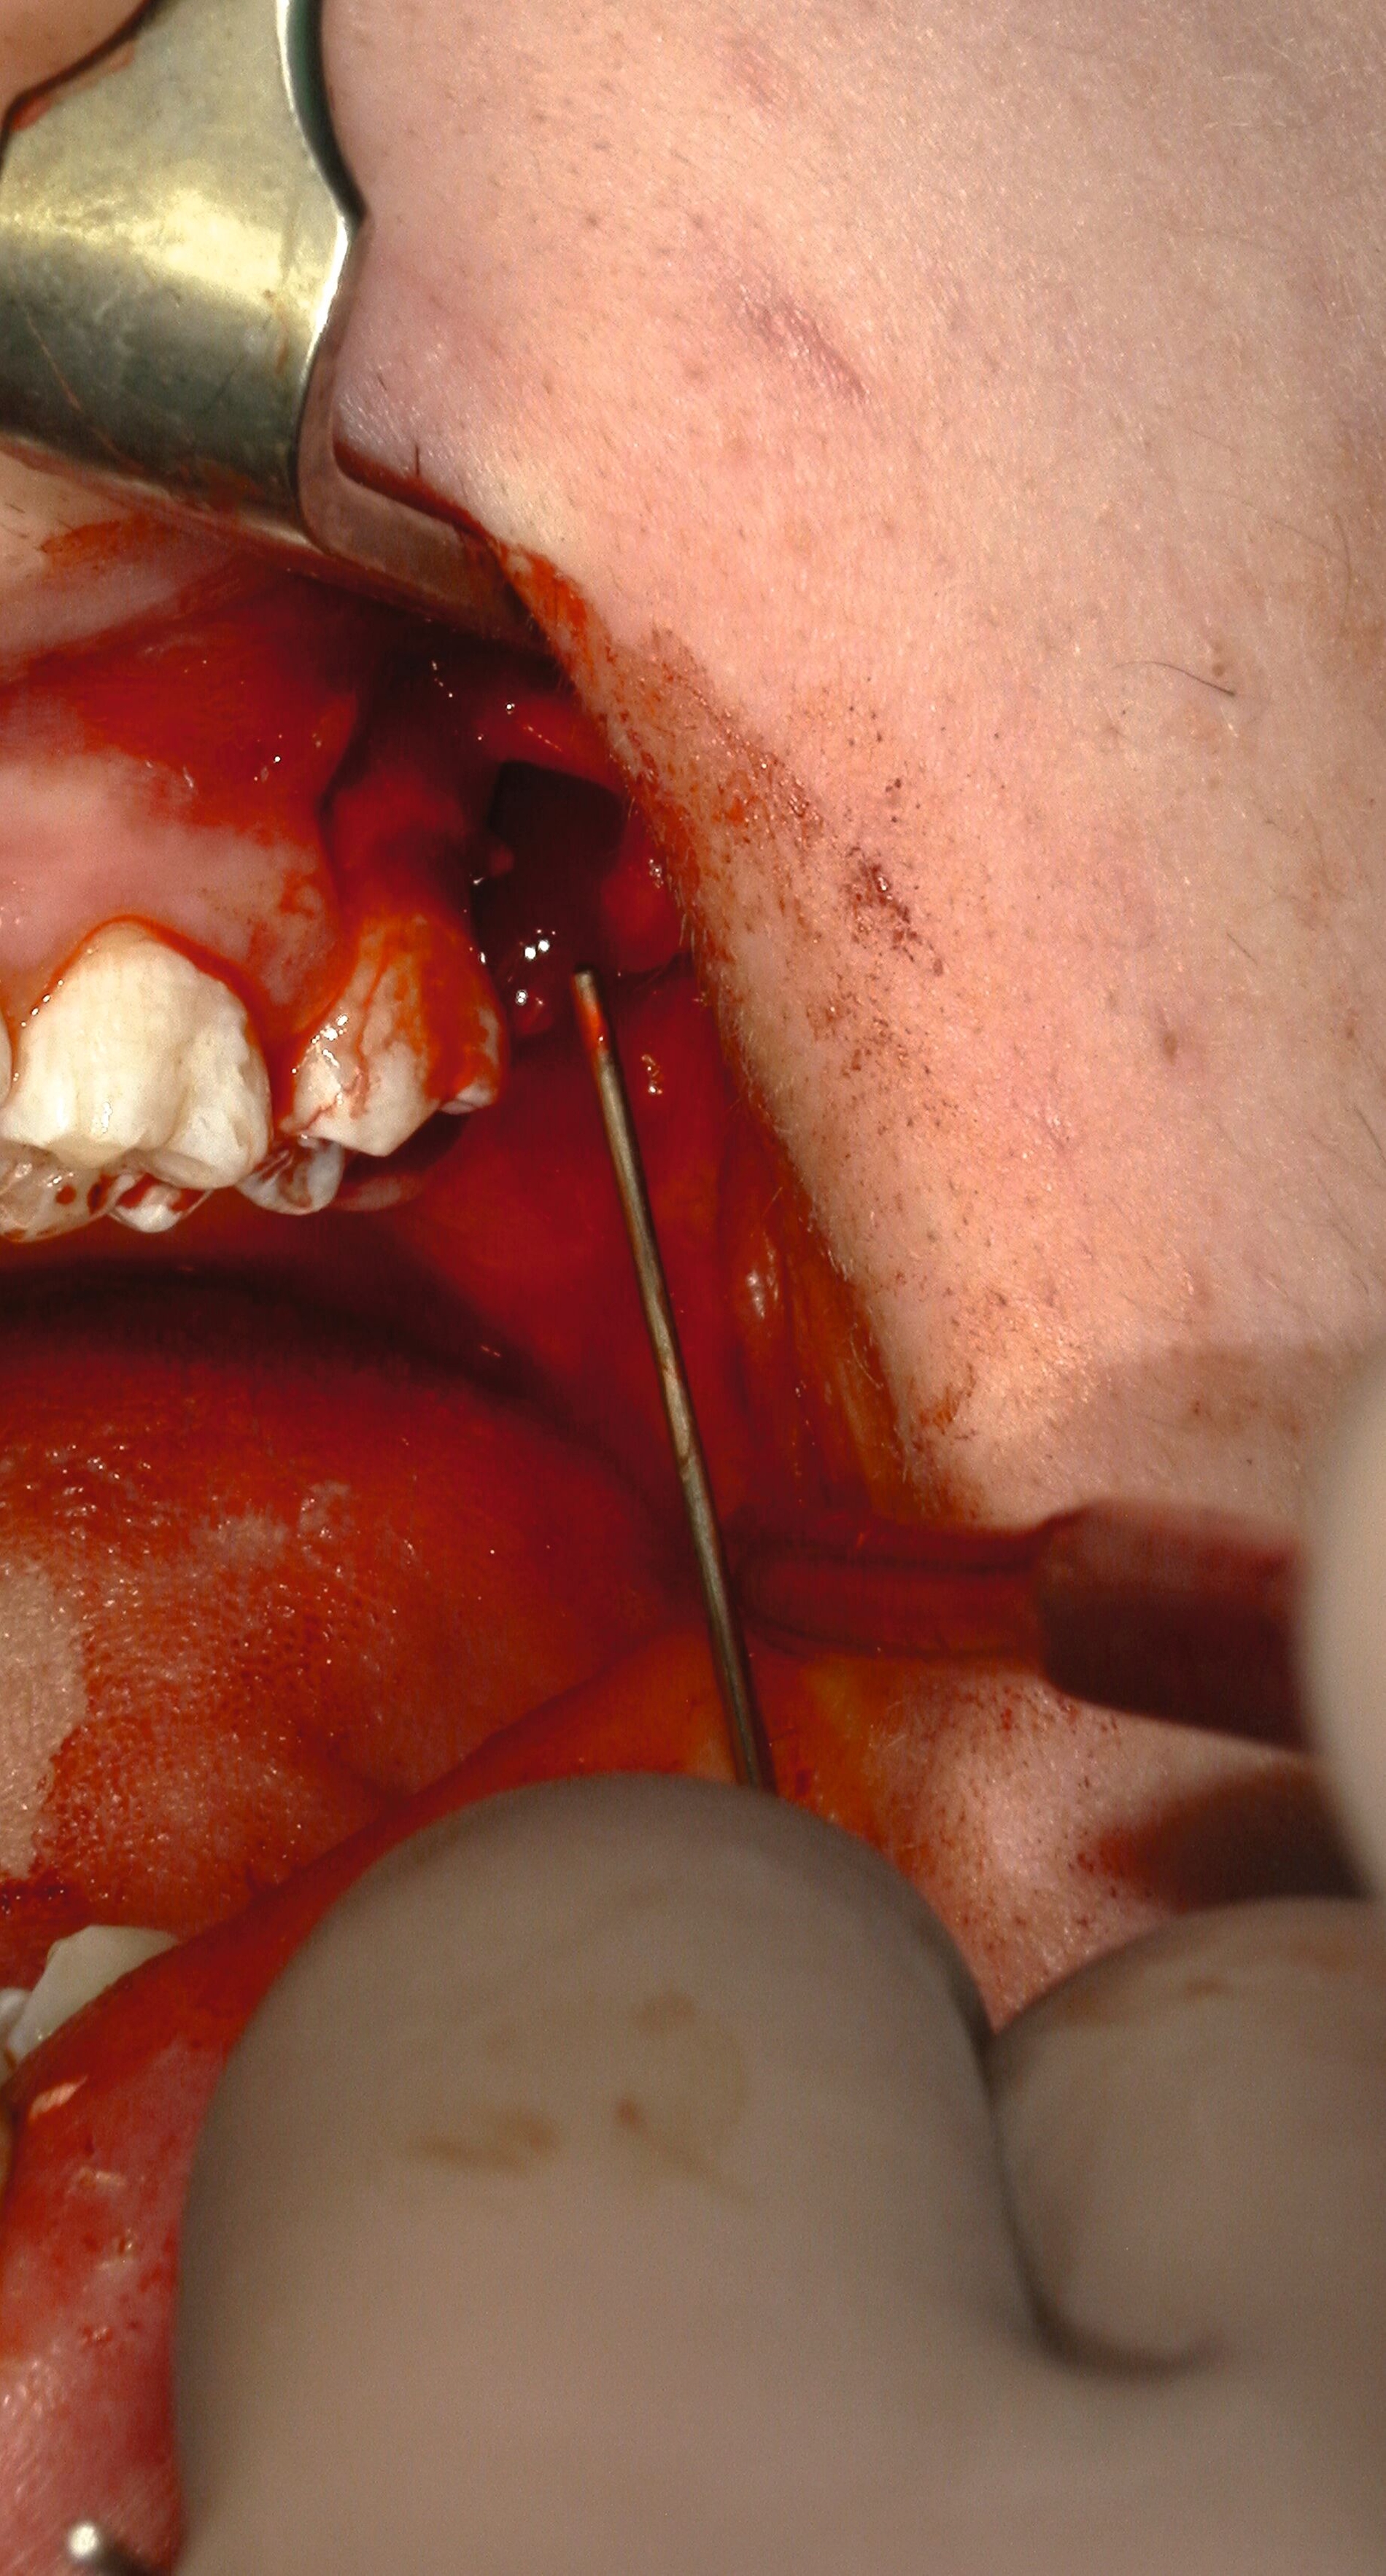

Allgemein kann eine präemptive Analgesie in Form einer präoperativen Gabe von 400-600 mg Ibuprofen eine Stunde vor dem Eingriff verabreicht werden, was sich positiv auf das Schmerzempfinden und den Bedarf postoperativ auswirken kann [Gutwald et al., 2019]. Zu Beginn des Eingriffs kann eine Lokalanästhesie durchgeführt werden. Bei dieser kommen entweder eine Oberflächenanästhesie, eine Infiltrationsanästhesie, eine Leitungsanästhesie (N. alveolaris inferior im Unterkiefer, N. palatinus major im Oberkiefer) oder eine intraligamentäre Anästhesie zum Einsatz (Abbildung 6) [Daubländer et al., 2016].

Da es aber in 20 bis 25 Prozent der Fälle zu Misserfolgen bei der Durchführung der Leitungsanästhesie des N. alveolaris inferior kommt, hat sich die sogenannte Gow-Gates-Technik als „hohe Leitung“ in den vergangenen Jahren mehr etabliert – deren Erfolgsrate liegt bei 95 Prozent. Dabei werden zusätzlich der N. lingualis, der N. mylohyoideus, der N. auriculotemporalis und der N. buccalis betäubt [Daubländer et al., 2016; Reed et al., 2012].

Zur Entfernung der unteren Weisheitszähne wird im Unterkiefer zunächst der aufsteigende Ast im Bereich der Linea obliqua palpiert. Verwendet man eine Pinzette zur Markierung (Abbildung 7), erfolgt die Schnittführung von dieser im senkrechten Winkel zum Knochen distal auf den zweiten Molaren zu, weiter im PA-Spalt bis mesial des zweiten Molaren. Liegt der Zahn tief verlagert oder anguliert, sollte man zur besseren Übersicht einen größeren Entlastungsschnitt unter Schutz des N. mentalis wählen.